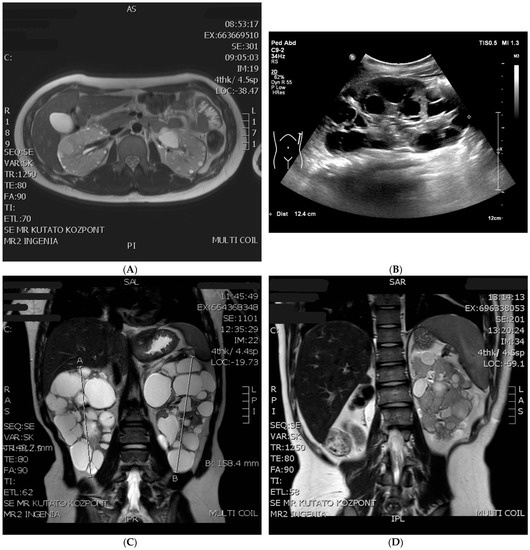

| Age at Examination | Kidney Size Right/Left (mm) | Largest Cyst Diameter in the Right/Left Kidney (mm) | Angiomyolipoma Size (mm) |

|---|---|---|---|

| 1 month | ND | 7/0 | 0 |

| 6 months | ND | 15/35 | 0 |

| 4 years | 112/113 | 33/52 | 0 |

| 6 years | ND | 40/50 | 0 |

| 9 years | ND | 38/37 | 0 |

| 11 years | 152/154 | 39/47 | 0 |

| 12 years | 150/160 | 50/52 | 0 |